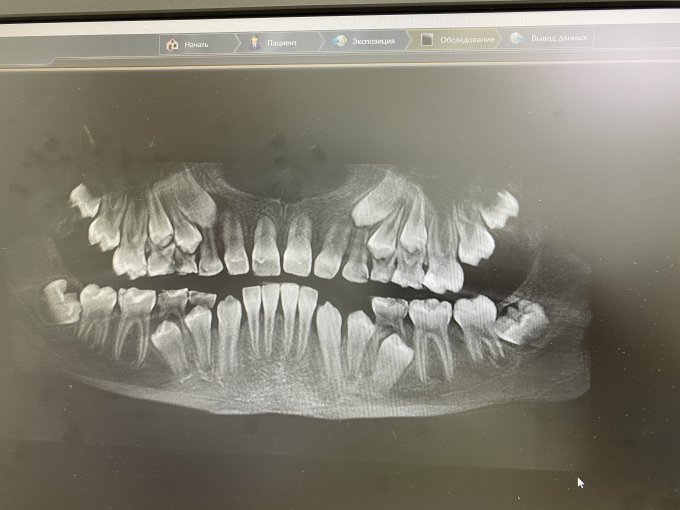

История со стоматологией приняла неожиданный оборот. Оказалось, пломба не «та самая», которую делали недавно, а реально давняя, да к тому же на молочном зубе.

Но так как теперь у меня в той клинике репутация крайне неприятной и недоговороспособной особы, то нас приняли как родных, осмотрели, сделали снимок, дали несколько квалифицированных рекомендаций по раскачиванию пары молочных зубов и направили как есть, без лечения, к детскому терапевту. Врач объяснила это тем, что она не работает с молочными зубами. Заверила меня, что несколько дней без пломбы сыну никак не навредят, и предположила, что зуб вообще пора удалить.

Снимок меня восхитил, публикую. Как человек далёкий от медицины, я такое видела впервые. Теперь для меня фраза «еще всё впереди» выглядит вот так.

Вася поржал, что у него как у акулы, зубы в три ряда. Главное его счастье — отпустили без сверления.